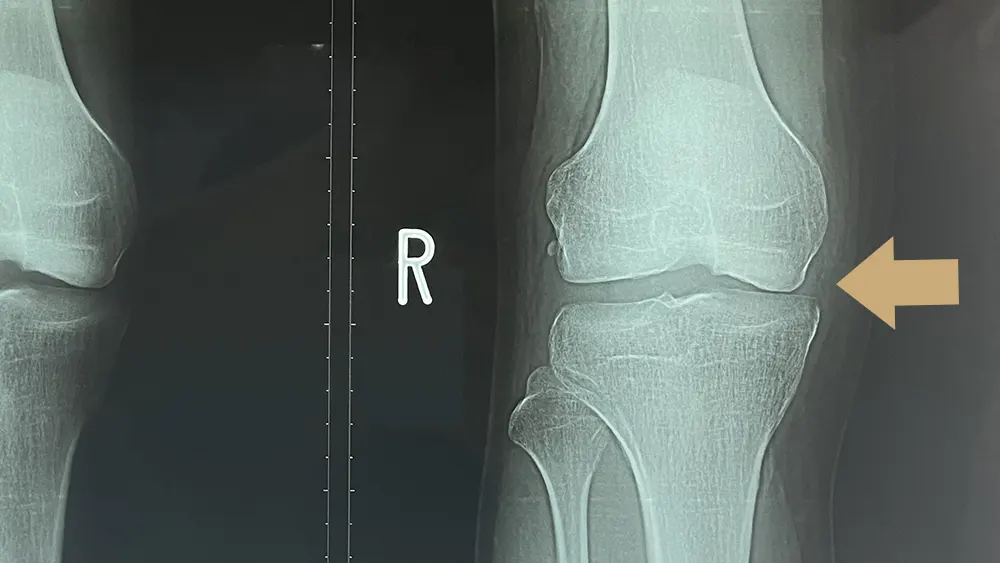

※内側半月板損傷しているレントゲン

半月板損傷と診断するためには、徒手検査や症状の経過からも可能ですが、単純X線(レントゲン)写真では半月板は写りません。

ただ、上の写真のように、長期にわたる負担のため損傷した場合には関節の隙間に差が生じることで判断できることもあります。